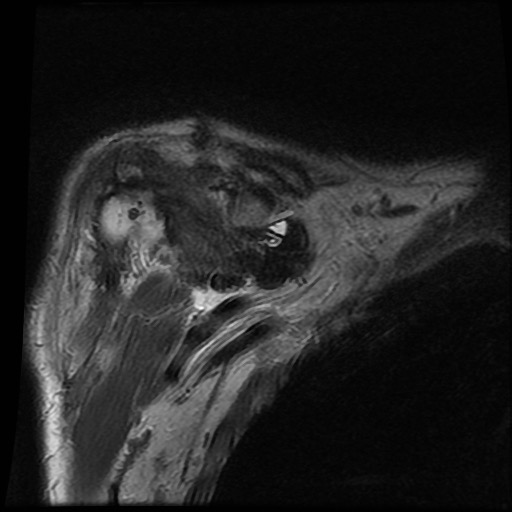

Hình ảnh MRI:

Tràn dịch lan tỏa tất cả các khớp cổ tay.

Phù tủy xương lan tỏa tất cả các xương cổ tay.

Bào mòn xương, ví dụ tại xương thuyền, xương đầu và xương móc.

Phá hủy khe khớp và sụn khớp, rõ nhất tại khớp STT và CMC4/5.